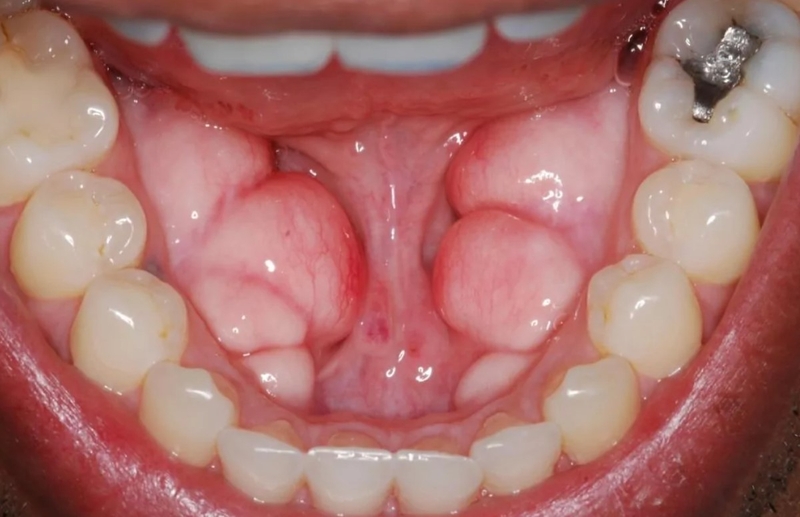

Torus hàm dưới (lồi xương hàm dưới) quan sát bằng mắt thường sẽ thấy như những khối u có bề mặt hơn tròn và nhẵn xuất hiện trong vòm miệng. Những cấu trúc này có rất nhiều hình dạng khác nhau, kích thước cũng có sự khác biệt, có thể nhỏ hoặc lớn tùy tình trạng bệnh.

Sự xuất hiện của các Torus hàm dưới khiến người bệnh không khỏi lo lắng, không biết lồi xương hàm dưới có sao không, có nguy hiểm không,…, đặc biệt là khi thấy những khối u này phát triển lớn hơn theo thời gian. Tuy nhiên, may mắn thay các khối u Torus hàm dưới hoàn toàn lành tính, không gây hại đối với sức khỏe. Không ít các trường hợp tồn tại khối u Torus cả cuộc đời nhưng không bị ảnh hưởng gì nghiêm trọng.